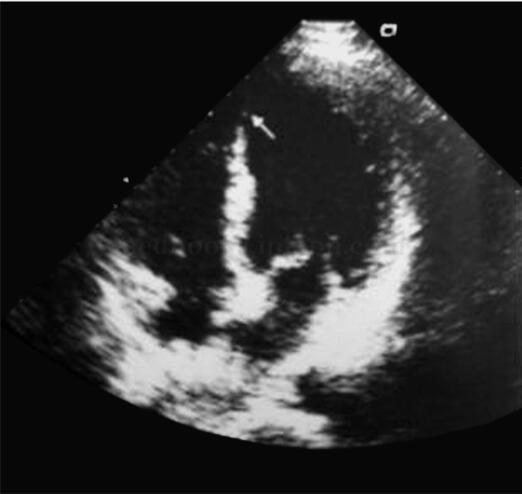

图2 超声心动图

心尖四腔切面示左心室心尖部室壁变薄,活动减弱

诊治经过:患者入院后第1份心电图(图1)示Ⅱ、Ⅲ及aVF导联ST段呈下斜行下移0.05mV,胸前导联T波形态基本正常,因外界干扰导致肢体导联显示不完全。但仔细分析可以发现,在V2导联有明显的“胚胎r波”,表现为r波纤细,其高度可能正常,但没有宽度。急性胸痛出现“胚胎r波”的患者,对急性心肌梗死的诊断具有很高的特异性。心肌标记物示MYO稍高于正常,CK‐MB及TnI正常。8:30查超声心动图示节段性室壁运动异常(室间隔中下段及左心室心尖部)(图2),因此尽管心脏标记物检查为阴性结果,临床考虑诊断为急性心肌梗死,9:40复查心电图,如图3所示。复查心肌标记物,CK‐MB 21.3ng/ml;MYO 468ng/ml;TnI 0.34ng/ml。诊断急性心肌梗死,急诊行冠状动脉造影示前降支100%闭塞,术中置入支架1枚。